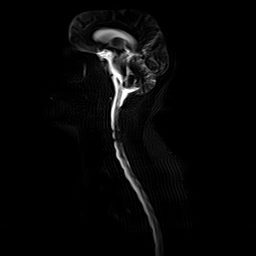

ام آر آی گردن با استفاده از انرژی آهنرباهایی قوی نصاویری از قسمت ستون فقرات که از گردن (ناحیه گردن ستون فقرات) عبور می کند، ایجاد می کند. ام آر آی از تششعات استفاده نمی کند.

در برخی از ام آر آی ها از رنگی مخصوص (داروی کنتراست) استفاده می شود. در بیشتر موارد این رنگ مخصوص از طریق سرمی در بازو یا دست شما قبل از تصویربرداری تزریق می شود. کنتراست از طریق تزریق نیز می تواند انجام شود. این رنگ به رادیولوژیست کمک می کند تا برخی از قسمت ها را بهتر ببیند.